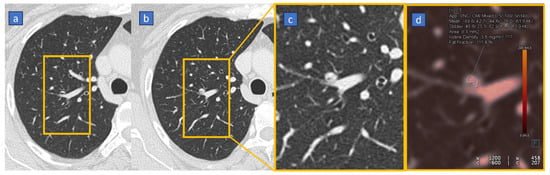

6. Lung Analysis

6.1. Pulmonary Thromboembolism

6.2. Lung Volumes and Perfusion